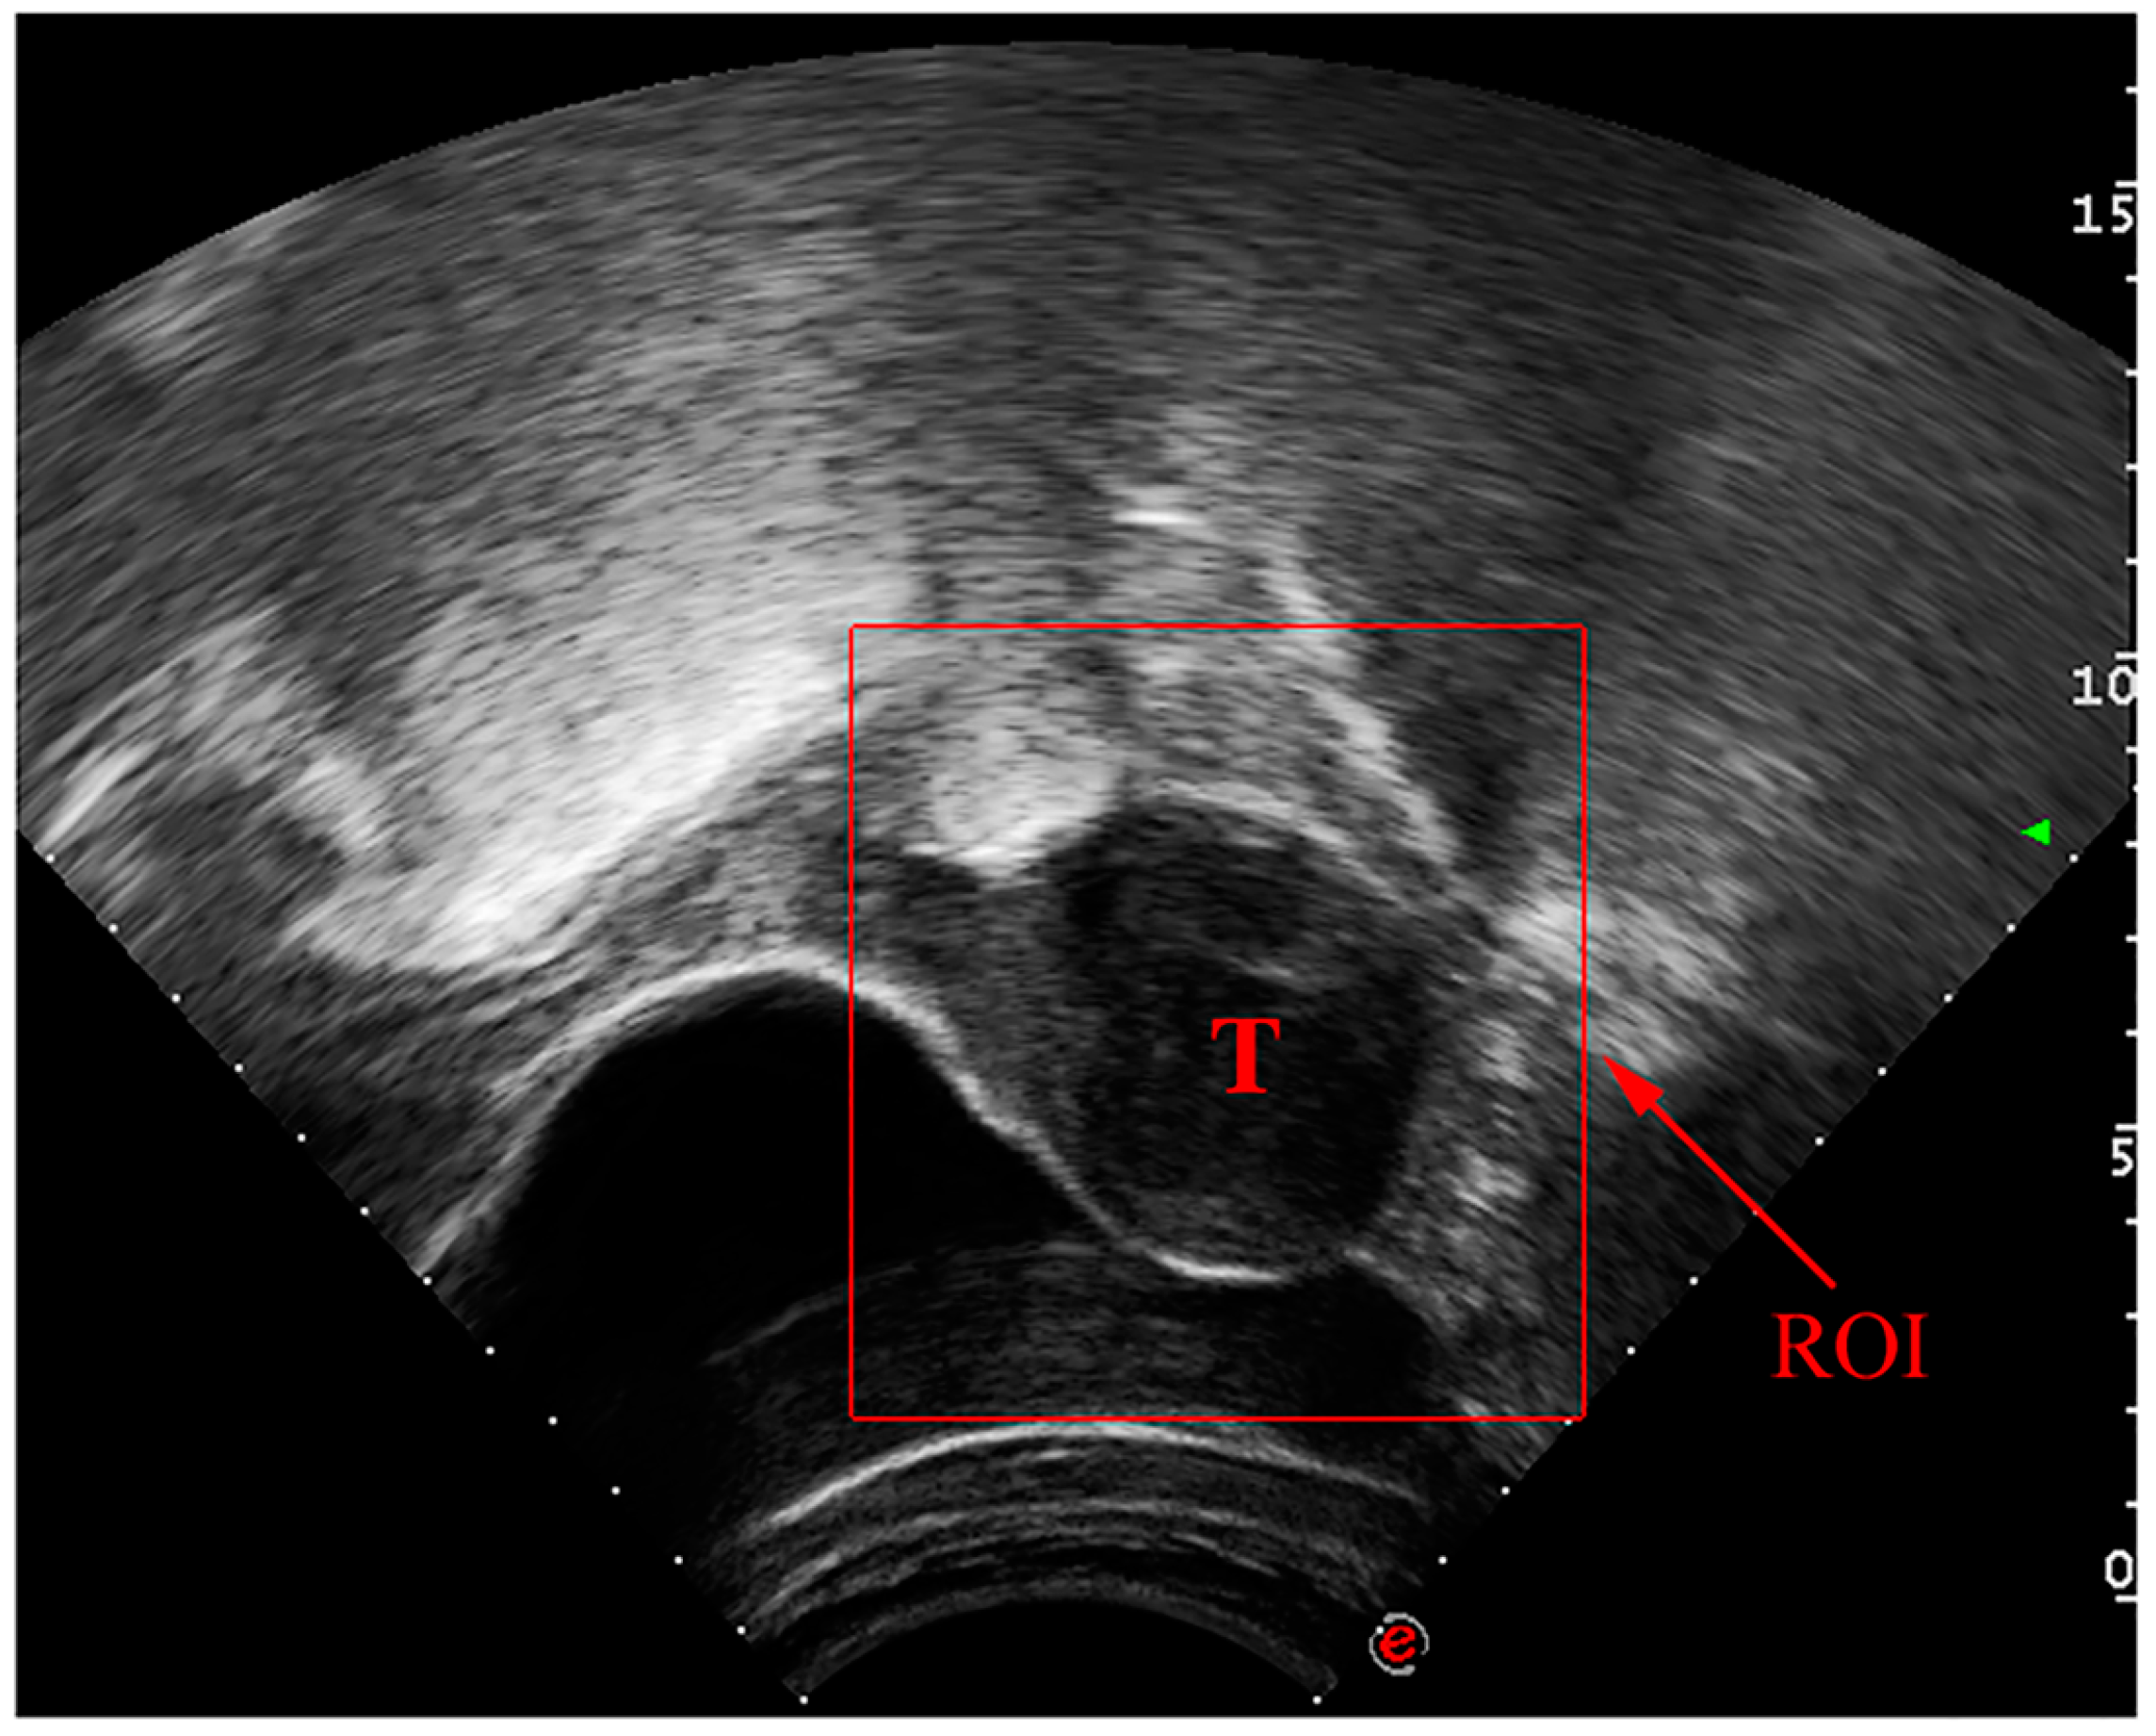

Manual identification of UF in ultrasound images is a laborious process that might vary from observer to observer. As reported in studies [7,8,9], significant progress has been made in the use of deep convolutional neural networks (DCNN) for automated medical image analysis tasks such as tumor detection and classification in ultrasound images. In Figure 1, a UF ultrasound scan is displayed with the region of interest (ROI) outlined in a square. These advances have the potential to improve patient outcomes by allowing for more precise, efficient, and reliable detection of UF in ultrasound images.

Figure 1. Ultrasound image of benign tumor of uterine fibroids.